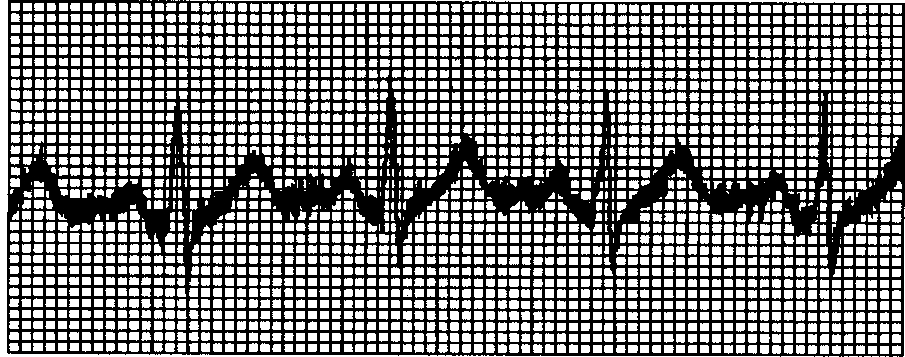

异常心电图图谱